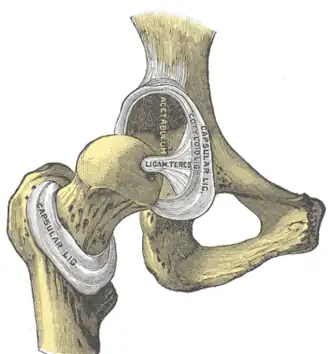

Hip-joint, front view

Hip-joint, front view -